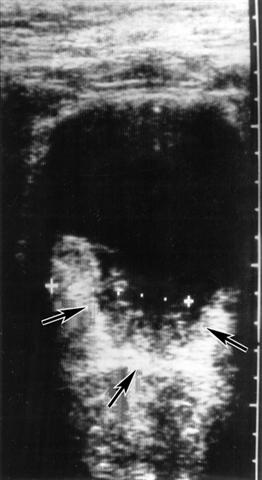

Рис. 5. Ультразвуковая томограмма при раке мочевого пузыря: стрелками указана опухоль.